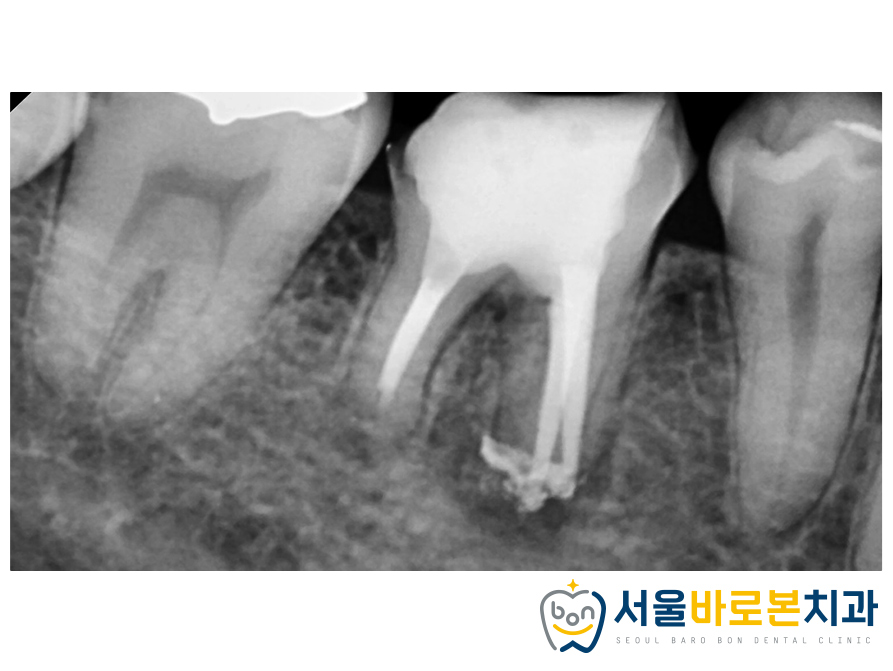

조금 더 자세하게 확인하기위해

크게 확대해서 촬영하는

치근단 사진을 촬영해보았고

뿌리 끝 하방의 염증을

한번 더 체크 하였습니다.